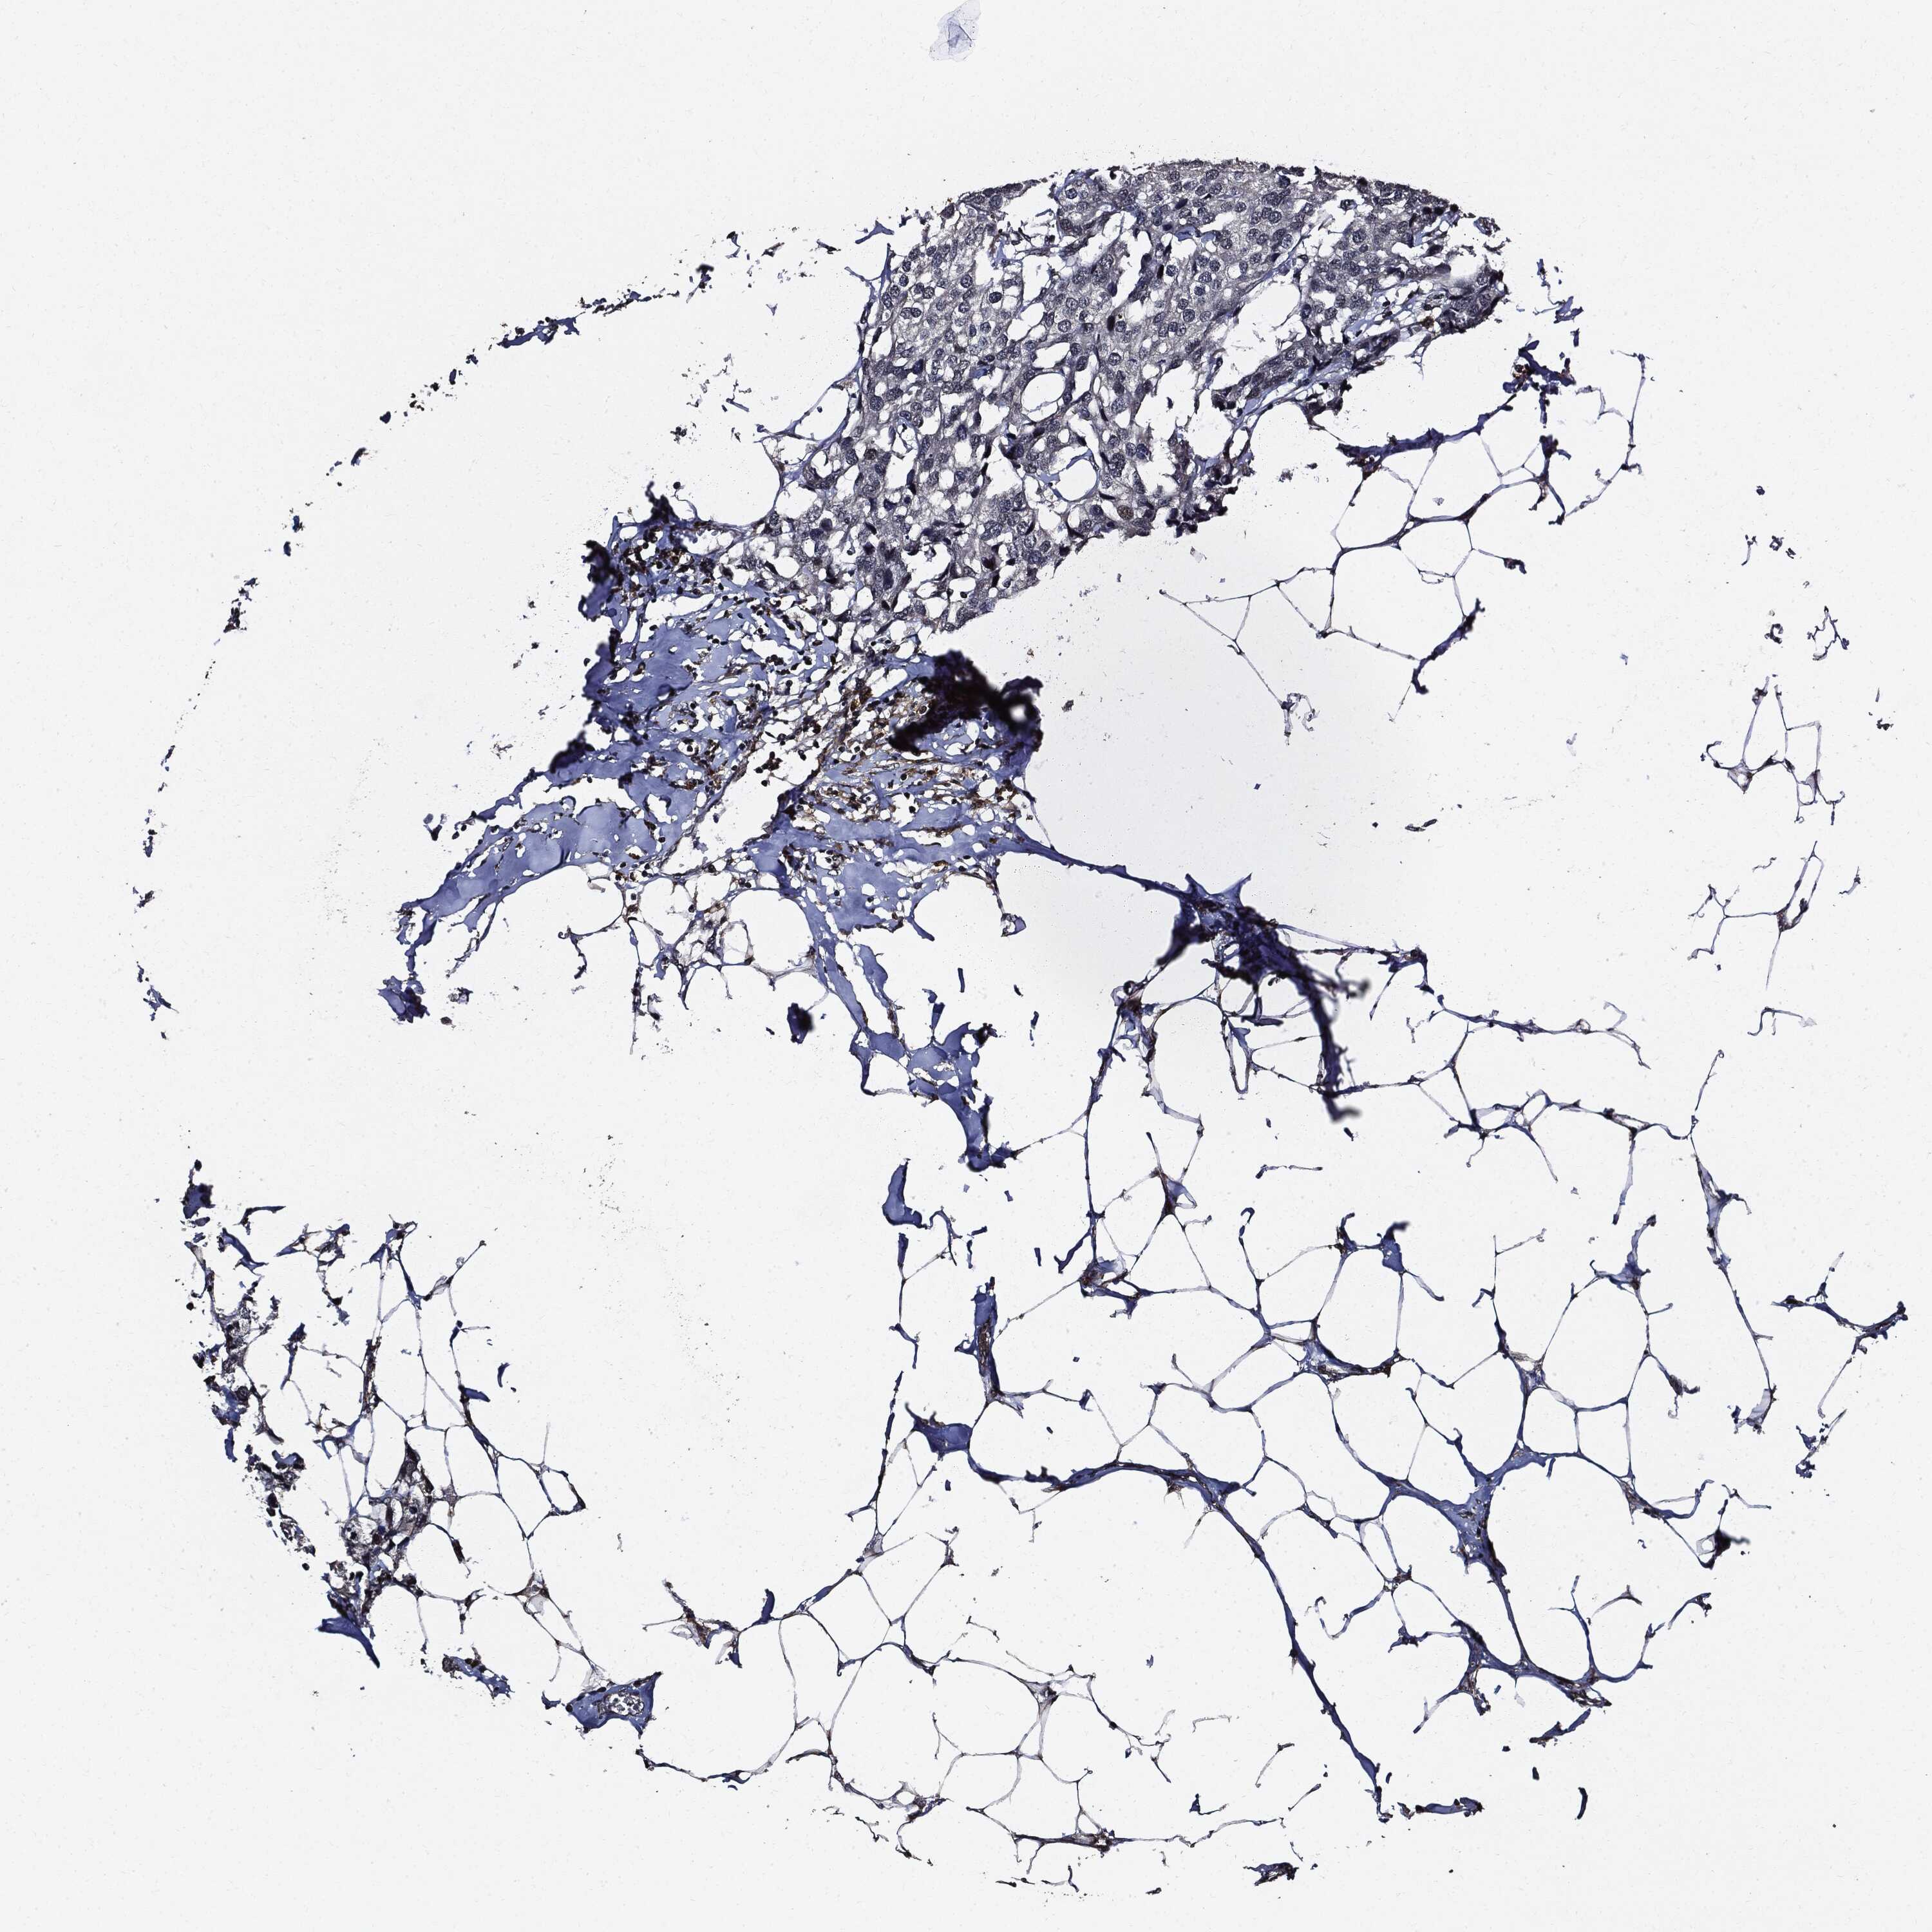

BRCA TCGA BRCA VALIDATION PROTEIN EXPRESSION

ANTIBODIES

AND

VALIDATION